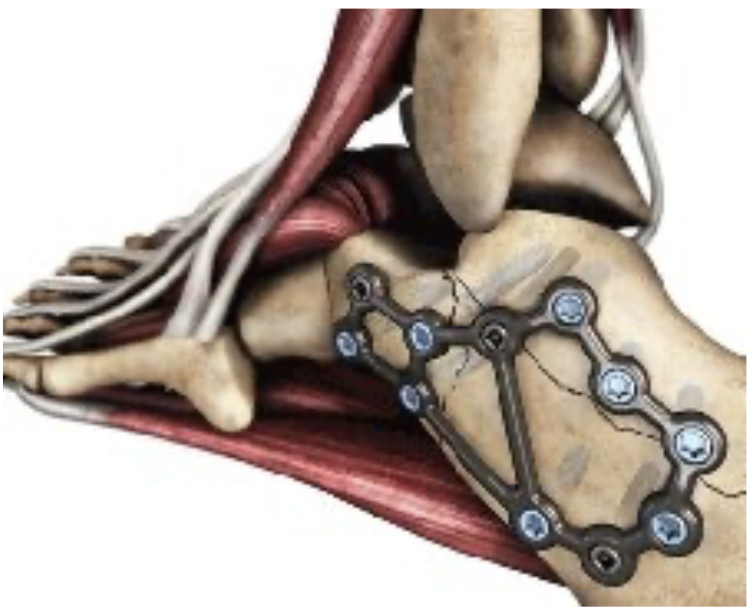

整形外科クリニックの後輩医師から鎖骨骨折の高齢の患者さんが手術を希望されて, 紹介されて受診されました. 飲酒後に転倒されて, 同じ側のあばら骨(肋骨)も3本骨折していました. 鎖骨の骨折は, 中央部で骨のかけら(骨片こっぺん)を生じた骨折で, AO/OTA分類では15.2Bでした(上図参照).

タバコを毎日20本吸っているヘビースモーカーでした. 呼吸機能と血液ガス分析(血液中の酸素量を調べる)検査を行ったところ, 呼吸機能の低下と血液中の酸素分圧が50 mmHg台(基準値は, 80〜100 mmHg)しかなく, すでに呼吸不全の状態でした. 何度か深呼吸をしていただいて, 再度血液ガス分析をしたところ, 酸素分圧が80 mmHg台に上がったので, 何とか全身麻酔が可能かと判断しました. 肋骨も折れているので, 痛みのため呼吸が浅くなって, 手術後に肺炎を起こして, 最悪死亡する可能性があることと, 手術で骨をつなげても, 喫煙すると新しい骨ができなくなるために, 骨折が治らない可能性があるので, 禁煙するのであれば手術を引き受けると告げました. 来週の水曜日に手術を予定しました.